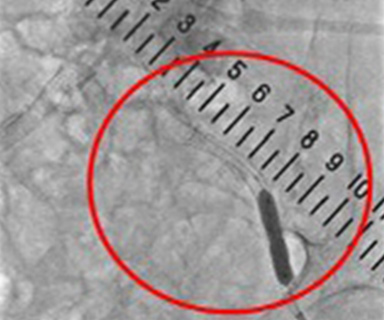

左側の画像は上腸間膜動脈と呼ばれる小腸や大腸の一部へ流入する動脈を造影して時間をおいて撮影し、門脈の血流を調べています。造影剤を血管内に注入すると目的の血管が黒く映ります。また肝細胞癌は肝動脈から多くの血流を取り込むため黒く染まってきます。治療前の撮影では赤丸の部分にうっすら黒い部分が肝細胞癌です。治療後の撮影では赤丸の部分に黒い部分がなくなっています。

門脈

(上腸間膜動脈下門脈造影)

治療前(右肝動脈造影)

治療後(総肝動脈造影)